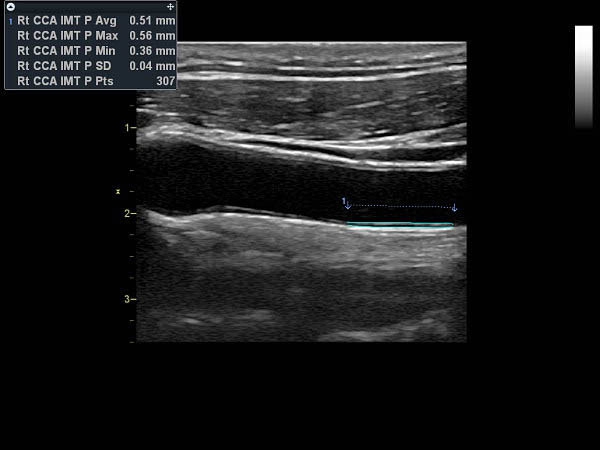

IMT (Intima Media thickness):

Да